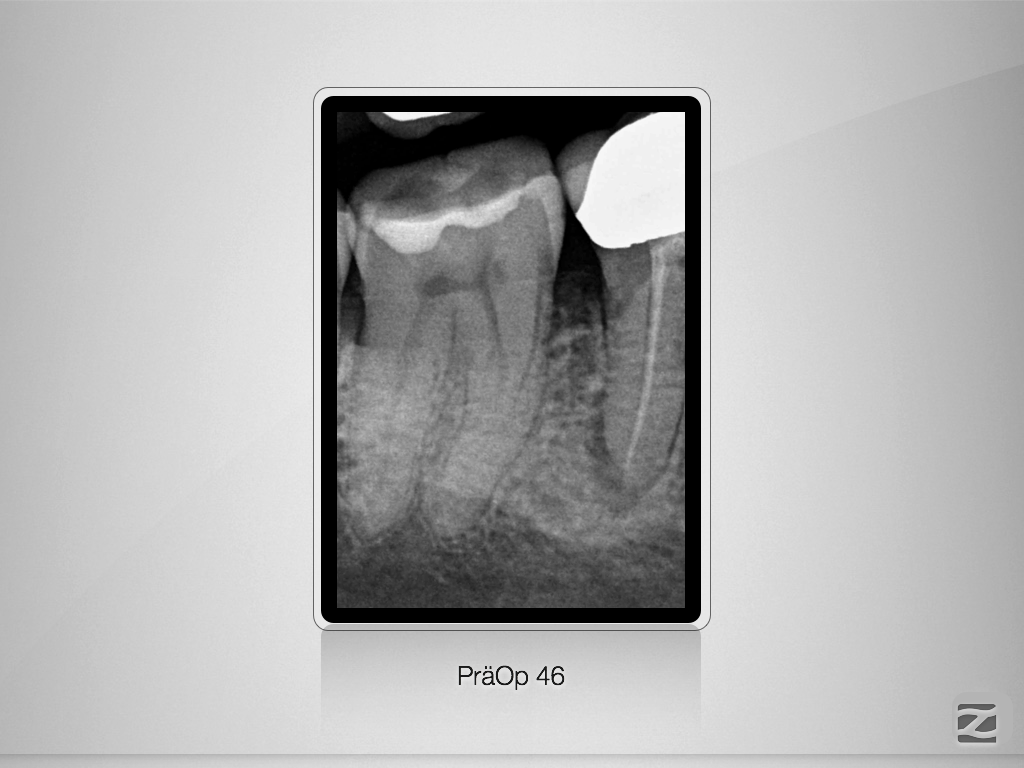

2D vs. 3D (XXVIV)